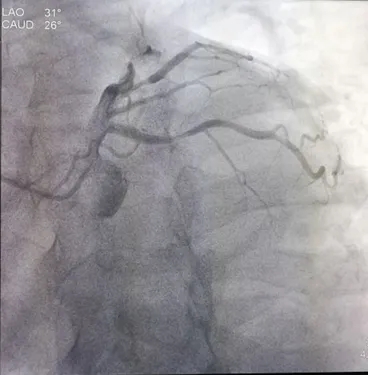

冠脉造影:入院第8天

蜘蛛位:LCX 中段70%狭窄;D2 近段70%狭窄。

造影结果:冠脉多支病变,LAD近、中段50%狭窄,LCX 中段75%狭窄,D2 近段70%狭窄RCA近段50%狭窄,PDA近段60%狭窄。

患者多支血管病变,行FFR检查LCX :0.78,D2:0.77治疗策略:暂可以不行PCI治疗,继续纠正心衰治疗。